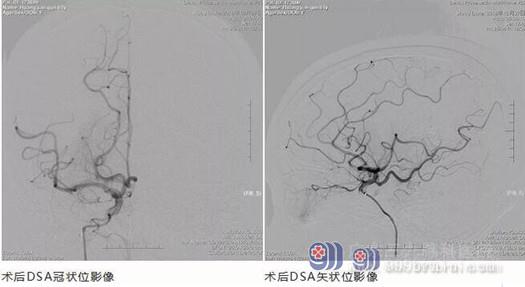

在神经内一科、介入室等科室的协力合作下,最终成功的将王阿姨脑血管中的血栓取出,恢复了脑部血供。当然,王阿姨发病的症状较重,而且从发病到取出栓子之间的时间间隔也较长,所以刚开始还要在监护室观察,但是随着王阿姨病情的稳定,几天之后就已经转入到普通病房中休养。

手术过了五天,神经内一科为王阿姨复查CT影像。可以看出,相比较手术前,右侧大脑中动脉的高密度影已经明显减轻了。